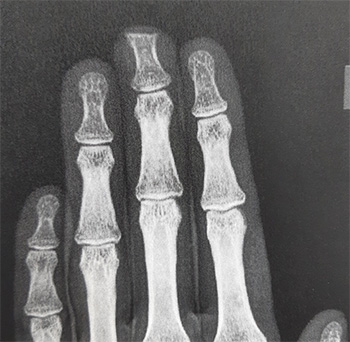

Por ejemplo, este caso se trata de una amputación parcial de pulpejo de 3er dedo mano izquierda, con una incorrecta regularización inicial .

Como se puede observar, había poco cojín graso en el pulpejo y marcadas espículas óseas que impedían que el paciente siquiera pudiera meter la mano en el bolsillo por dolor al mínimo roce de la punta del dedo.

Finalmente, el tratamiento efectuado fue regularizar los márgenes óseos, acortar la longitud de la falange y aumentar el soporte graso del pulpejo con un pequeño colgajo de avance.